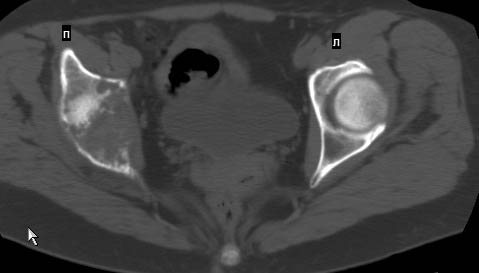

Сохранная по соматической патологии женщина ,47 лет. В 1996 г. установлен диагноз- cr левой молочной железы Т2N1Mo (2б)- проведено комплексное лечение- мастэктомия по Холстеду, ДГТ, 5 курсов ПХТ по схеме CMF. Сейчас менопауза уже 6-7 лет. В декабре 2004 года на профилактической остеосцинтиграфии с Тс99- выявлен единичный очаг повышенной фиксации препарата в зоне правой седалищной кости, рекомендована Рентгенография костей таза, выполнена- без патологии. УЗИ брюшной полости и Р-графия легких от конца апреля 2005 года - без патологии. Приблизительно 3 месяца назад появился болевой синдром в правом т/бедренном суставе с тенденцией к усилению. На рентгенограмме таза от мая 2005 года по заключению Рентгенолога очагов остеодеструкции не выявлено. Сегодня сделал ей Кт костей таза (картинки в приложении)- очаг деструкции в правой седалищной кости в зоне крыши вертлужной впадины.Что можно и нужно сделать? Жду советов, мнений, предложений по дальнейшей тактике ведения больной. С уважением, Корнев А.В.